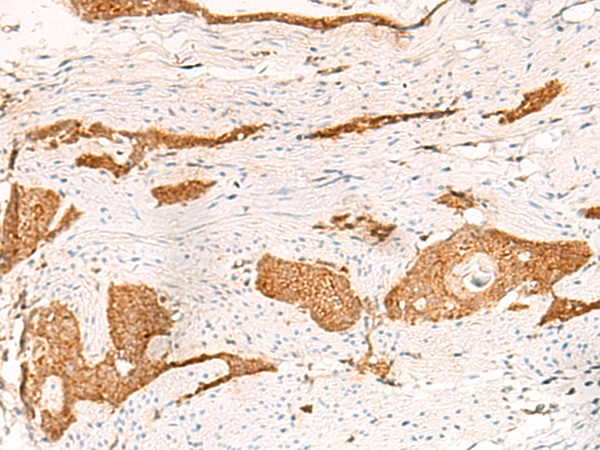

The image is immunohistochemistry of paraffin-embedded Human liver cancer tissue using 47367(THNSL1 Antibody) at dilution 1/70.(Original magnification: 200)

The image is immunohistochemistry of paraffin-embedded Human esophagus cancer tissue using 47367(THNSL1 Antibody) at dilution 1/70.(Original magnification: 200)